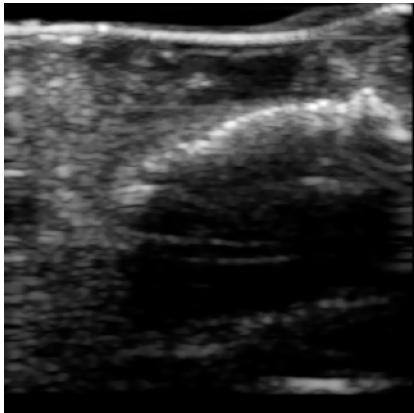

Chronic wounds including diabetic and arterial/venous insufficiency injuries have become a major burden for healthcare systems worldwide. Demographic changes suggest that wound care will play an even bigger role in the coming decades. Predicting and monitoring response to therapy in wound care is currently largely based on visual inspection with little information on the underlying tissue. Thus, there is an urgent unmet need for innovative approaches that facilitate personalized diagnostics and treatments at the point-of-care. It has been recently shown that ultrasound imaging can monitor response to therapy in wound care, but this work required onerous manual image annotations. In this study, we present initial results of a deep learning-based automatic segmentation of cross-sectional wound size in ultrasound images and identify requirements and challenges for future research on this application. Evaluation of the segmentation results underscores the potential of the proposed deep learning approach to complement non-invasive imaging with Dice scores of 0.34 (U-Net, FCN) and 0.27 (ResNet-U-Net) but also highlights the need for improving robustness further. We conclude that deep learning-supported analysis of non-invasive ultrasound images is a promising area of research to automatically extract cross-sectional wound size and depth information with potential value in monitoring response to therapy.